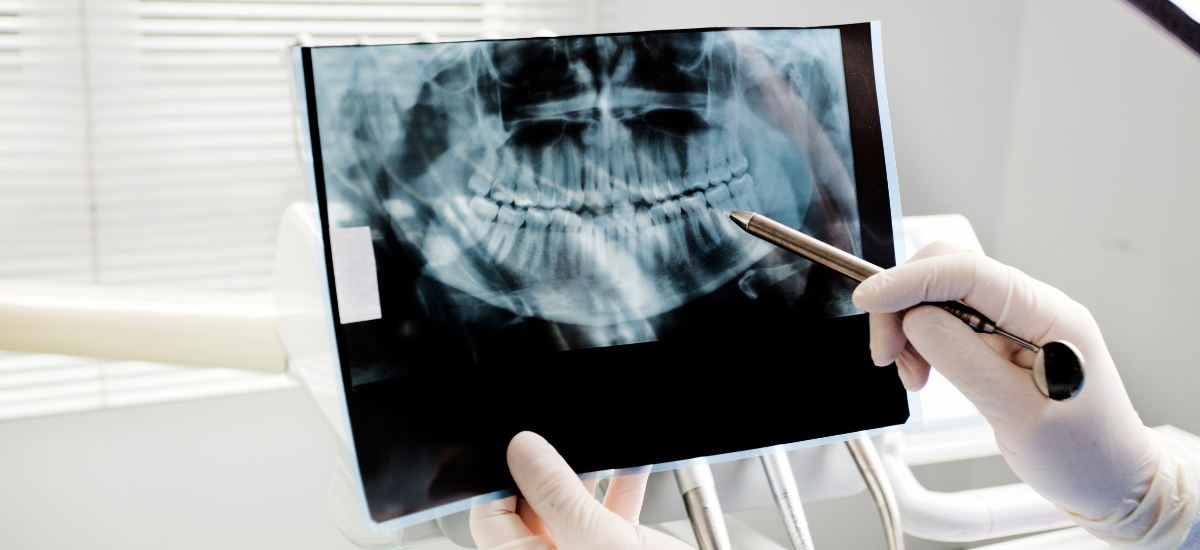

インプラント治療を安全に進めるためには、事前の診断が非常に重要です。診断では、口腔内の状態を確認するだけでなく、顎の骨の形や量、神経や血管の位置などを詳しく把握する必要があります。

そのため多くの歯科医院では、歯科用CTを用いた三次元的な画像診断が行われています。CT画像をもとに骨の厚みや密度を確認することで、インプラントを埋入できる位置や角度をより正確に検討することができます。

歯科用CT検査で確認する重要なポイント

インプラント治療の適応を判断するためには、顎の骨の状態を正確に把握することが重要です。その際に用いられるのが歯科用CT検査です。

CT検査では、顎の骨の高さや幅、骨密度、神経や血管の位置などを三次元的に確認することができます。これにより、インプラントを安全に埋入できる位置や角度を事前に計画することが可能になります。

また、骨の形態や厚みを詳しく確認することで、骨造成などの追加治療が必要かどうかを判断する材料にもなります。レントゲンだけでは分からない立体的な骨の情報を把握できる点が、CT検査の大きな役割です。

インプラントは顎の骨に固定される治療であるため、骨の量や質が重要な判断基準となります。歯科用CTによる精密な診断を行い、骨の状態を正確に把握することが安全な治療計画につながります。

CT検査と診断が果たす役割

インプラント治療の適応を判断する際には、歯科用CTによる検査が重要な役割を果たします。通常のレントゲンでは平面的な情報しか得られませんが、CT検査では顎の骨の量や厚み、神経や血管の位置などを立体的(3次元)に確認することができます。

これにより、インプラントを安全に埋入できる位置や角度、必要な骨量などをより正確に評価することが可能になります。また、骨が不足している場合には骨造成などの追加治療が検討できるかどうかも、この検査をもとに判断されます。

インプラントの適応は見た目や症状だけでは判断できないため、CTによる客観的なデータに基づく診断が安全性と長期的な安定性につながります。